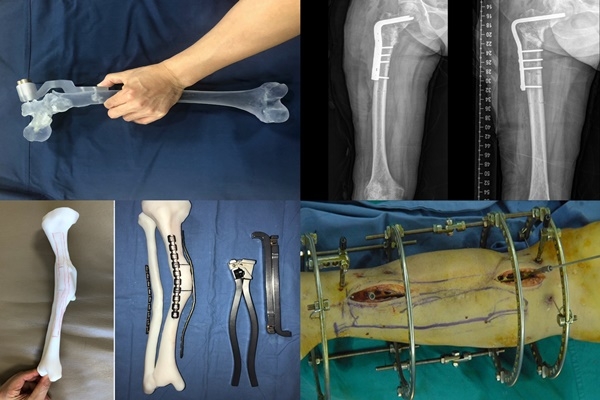

- 폐쇄성 골절: 피부나 점막이 손상되지 않고, 뼈가 내부에 있는 상태로 파열되는 골절입니다. 외부에서 드러나지 않고 피부 아래에 숨겨진 상태로 발생합니다. 이러한 종류의 골절은 치료 및 회복 기간이 비교적 짧을 수 있으며, 감염 위험이 낮습니다.

- 개방성 골절: 이는 피부나 접근 가능한 점막이 손상되어 외부 환경과 연결된 상태에서 뼈가 파열되는 골절을 의미합니다. 피부 상처로 인해 각종 세균과 같은 병원체들이 부상 부위로 진입할 수 있어 감염 위험이 큽니다.

골절 치료: 폐쇄성 골절의 경우

'원위지골의 폐쇄성 골절' 진단을 받은 경우에는 일반적으로 통원치료나 입원 치료를 받게 됩니다. 피부가 찢어지지 않은 폐쇄성 골절의 경우, 감염 위험이 낮아 치료가 비교적 간단할 수 있습니다. 통원치료를 선택할 경우, 부어진 부위를 안정화시키고, 통증을 줄이기 위한 약물 치료와 물리치료가 진행됩니다.